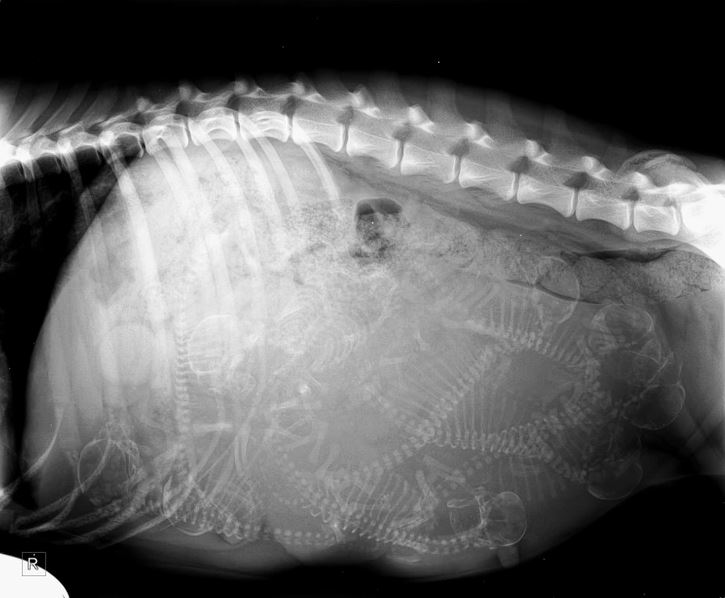

#15 Röntgenový snímok kotnej fenky mojej sestry